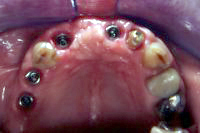

In der Front und im Seitenzahngebiet wurden je zwei Implantate gesetzt (Abb. 1). In der Front musste Knochen seitlich (transversal) und im Seitenzahngebiet vertikal (siehe Sinuslift, komplexe Implantologie) aufgebaut (augmentiert) werden.